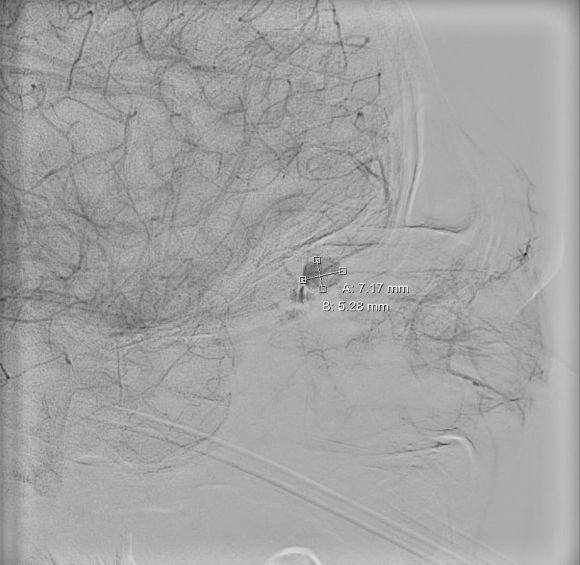

Subsequent Cerebral Angiogram demonstrating the one of the two OAPA located at the middle right ophthalmic artery measuring about 7.17*5.28mm without active extravasation, confirming the diagnosis of OAPA. Due to proximity to the right central retinal artery, endovascular embolization was deferred.